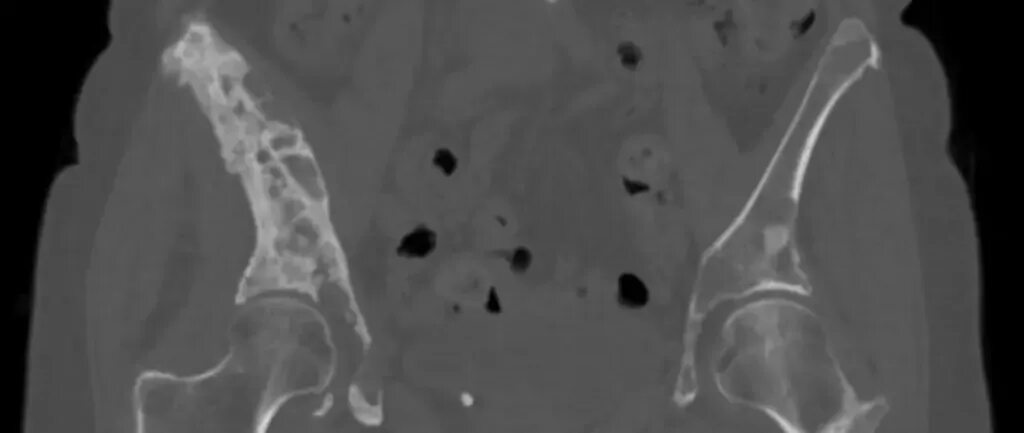

Вероятность метастаз